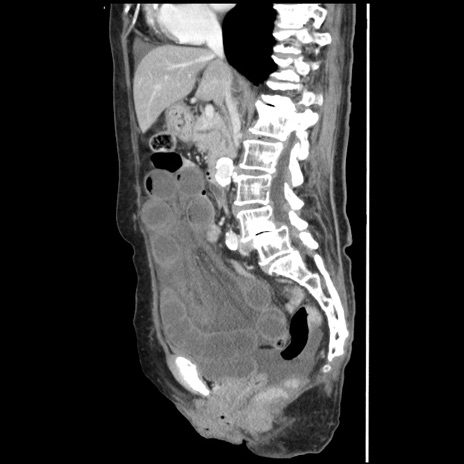

横断像

【症例】80歳代女性

【主訴】腹痛

【現病歴】8時間前から腹痛あり来院。

【既往歴】糖尿病、脂質異常症、子宮体癌にて子宮全摘術

【身体所見】意識清明・会話良好だが腹痛で苦悶様、全腹部にわたって反跳痛と圧痛あり

【データ】WBC 13600、CRP 0.14、LDH 224、CK 90